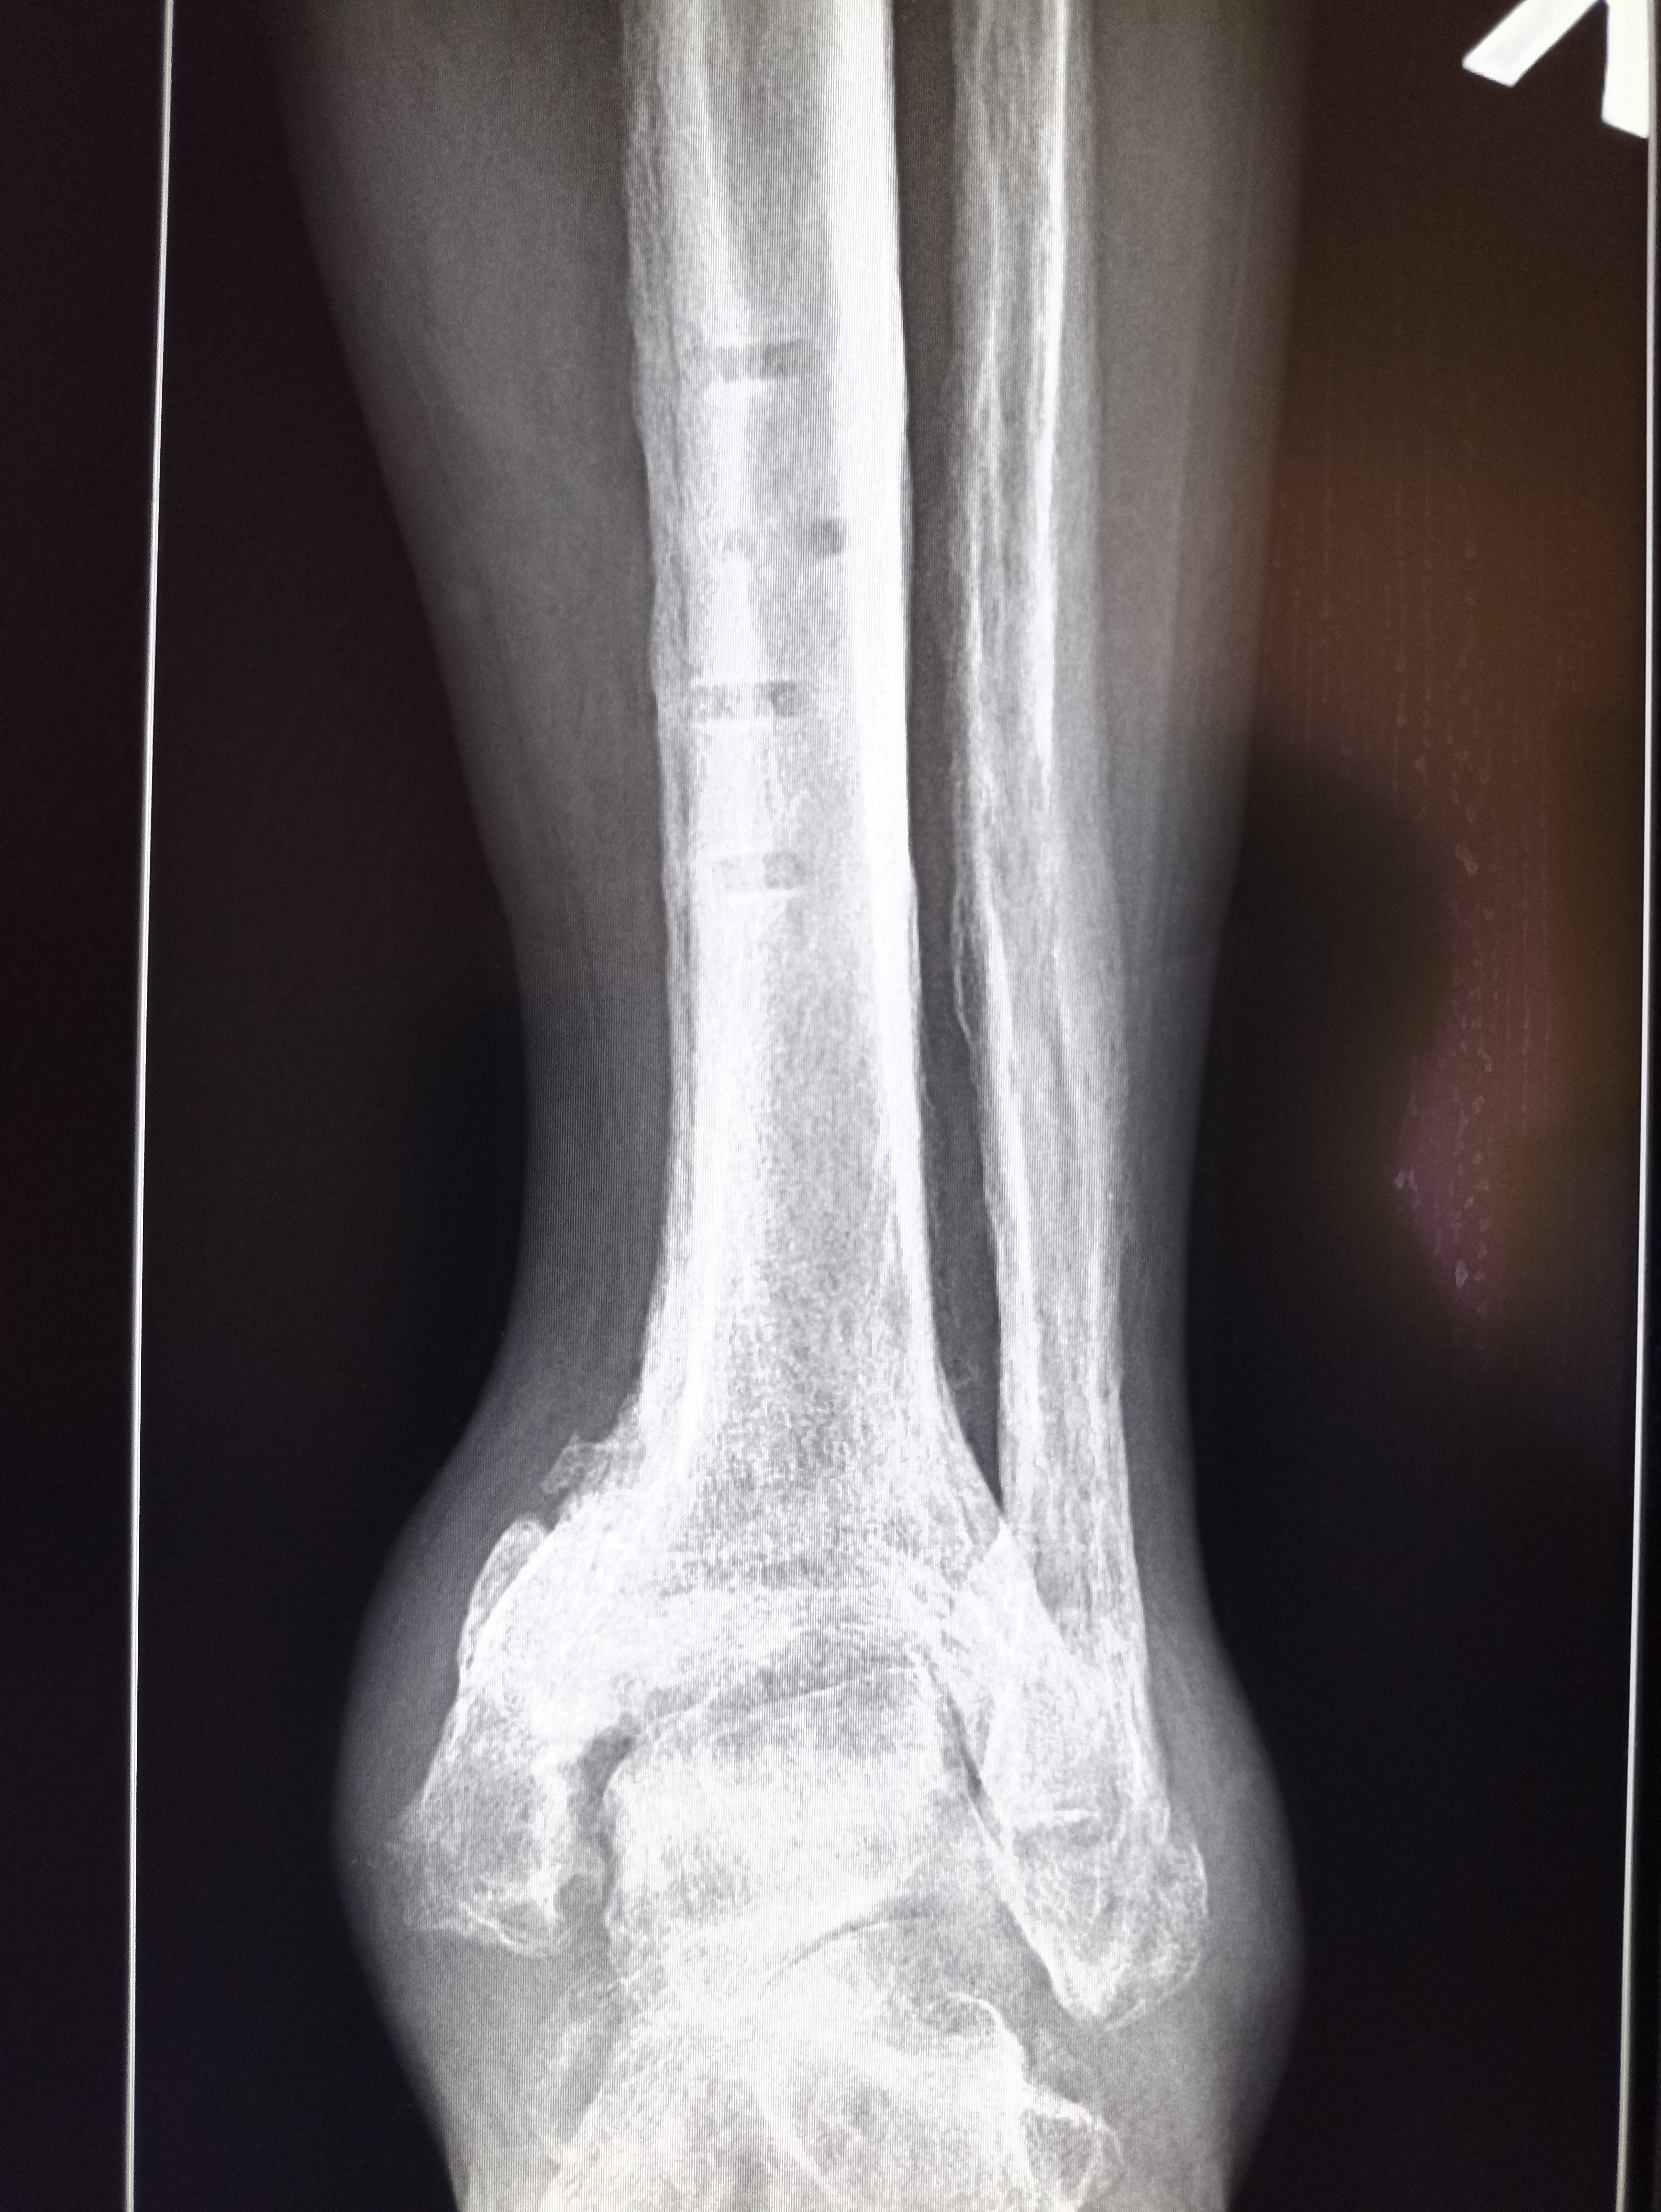

И снова здравствуйте! Сегодня! В этом тредике! Мы будем с вами общатся и играть в доктора! Я буду вам постировать фоточки, а вы угадывать пиздецомы! Я все еще нихуя не успеваю, пытаюсь описать за 25 число, сегодня задержусь наверное после работы опять пытаясь нагнать нагрузку :-(